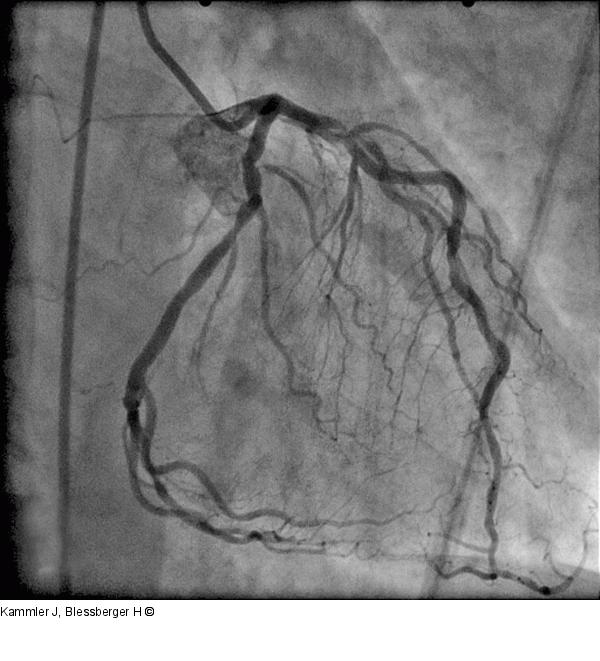

Abbildung 11: Angiogramm Angiogramm des Patienten 2: Visuell grenzwertige Lumeneinengung in der Mitte des Ramus circumflexus mit negativer FFR (0,96) |

Angiogramm des Patienten 2: Visuell grenzwertige Lumeneinengung in der Mitte des Ramus circumflexus mit negativer FFR (0,96) |